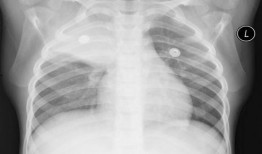

你有没有听说?2025年的胸片爆料来啦!没错,就是那个能让你一窥未来科技风采的胸片。今天,就让我带你从多个角度来揭秘这个神秘的新...